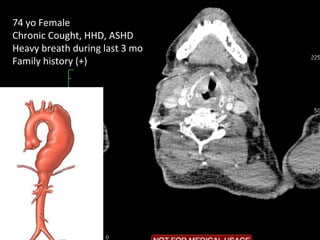

74 yo Female

Chronic Cought, HHD, ASHD

Heavy breath during last 3 mo

Family history (+)

Total

debranching